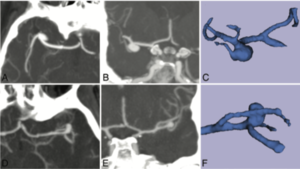

Association Between Vascular Anatomy and Posterior Communicating Artery Aneurysms

Publication: World Neurosurg. 2015 Nov;84(5):1251-5. PMID: 26074436 Authors: Can A, Ho AL, Emmer BJ, Dammers R, Dirven CM, Du R. Institution: Department of Neurosurgery, Brigham and Women's Hospital, Harvard Medical School, Boston, MA, USA. Background/Purpose: Hemodynamic stress, conditioned by the geometry and morphology of the vessel trees, plays an important role in the formation of intracranial aneurysms. The aim of this study was to identify image-based location-specific morphologic parameters that are associated with posterior communicating artery (PCoA) aneurysms. Methods: Morphologic parameters obtained from computed tomography angiography of 56 patients with PCoA aneurysms and 23 control patients were evaluated with 3D Slicer, an open-source image analysis software, to generate 3-dimensional models of the aneurysms and surrounding vasculature. Segment lengths, diameters, and vessel-to-vessel angles were examined. To control for genetic and clinical risk factors, the unaffected contralateral side of patients with unilateral PCoA aneurysms was used as a control group for internal carotid artery (ICA)-related parameters. A separate control group with visible PCoAs and aneurysms elsewhere was used as a control group for PCoA-related parameters. Results: Internal carotid artery-related parameters were not statistically different between the PCoA aneurysm and control groups. Univariate and multivariate subgroup analysis for patients with visualized PCoAs demonstrated that a larger PCoA diameter was significantly associated with the presence of a PCoA aneurysm (odds ratio = 12.1, 95% confidence interval = 1.3-17.1, P = 0.04) after adjusting for other morphologic parameters. Conclusions: Larger PCoA diameters are associated with the presence of PCoA aneurysms. These parameters may provide objective metrics to assess aneurysm formation and growth risk stratification in high-risk patients. |